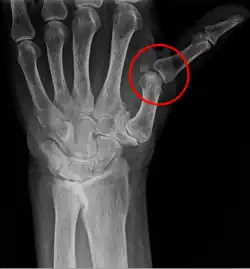

Subluxation bezeichnet eine unvollständige Ausrenkung eines Gelenkes, wobei der verschobene Gelenkkopf sich noch teilweise in der Gelenkpfanne befindet. Typische, meist mit einer Instabilität des Gelenkes verbundene, Fälle sind beispielsweise: